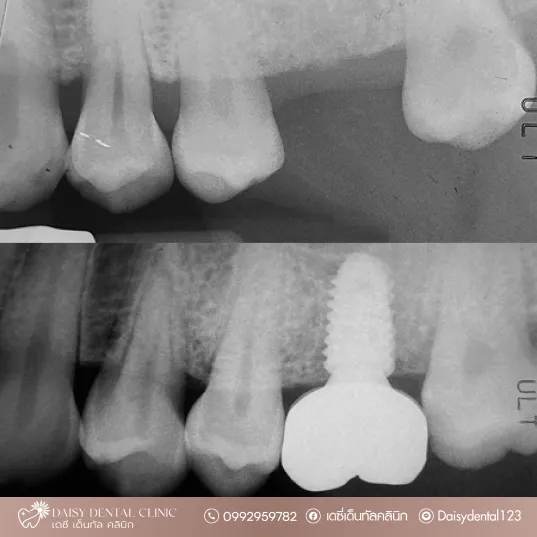

ผลงานของเรา

เดซี เด็นทัล คลินิก